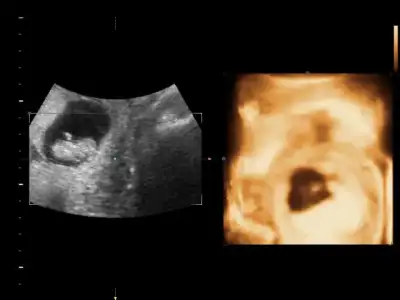

Canım doktorun erkek dediği resmi de koyar mısın?Bebeğimin cinsiyeti belli oldu ERKEK